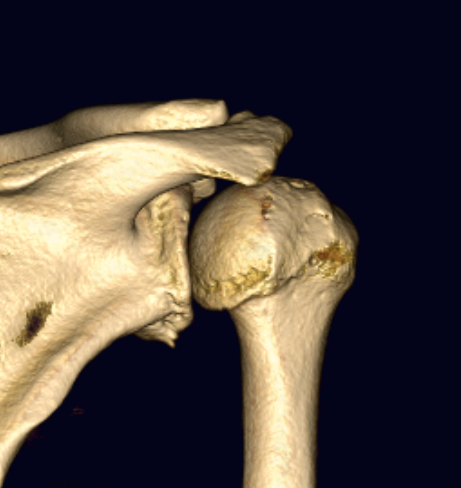

Hill Sachs

Hill Sachs 3D CT

Hill Sachs lesion